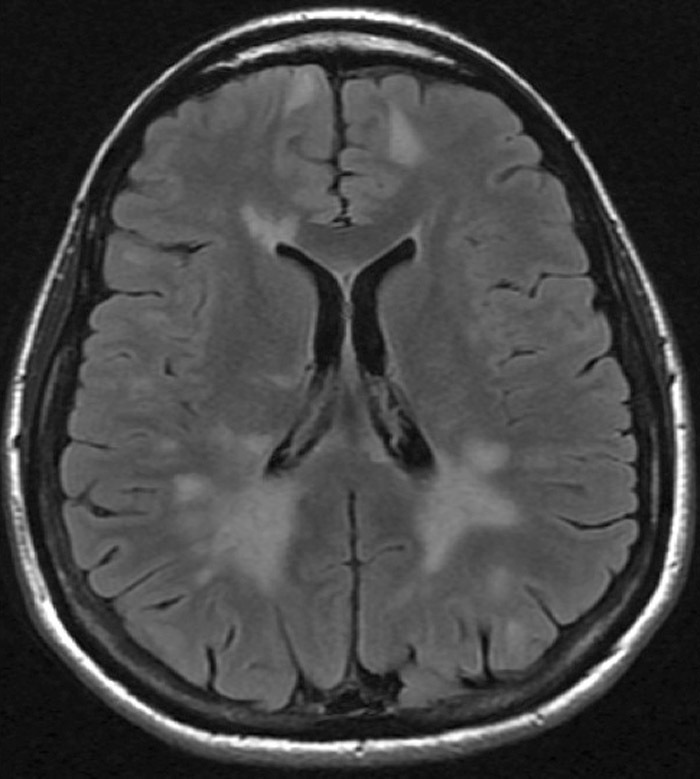

Il s’agit d’une IRM cérébrale en coupe axiale, séquence FLAIR montrant des hypersignaux diffus en plage périventriculaire typique d’une sclérose en plaques.

En révélant la dissémination spatiale des lésions de démyélinisation, l’IRM permet un diagnostic de la maladie dès le premier épisode clinique évocateur. La sclérose en plaques est une maladie complexe inflammatoire, démyélinisante et dégénérative. Les traitements disponibles dans cette affection sont actifs sur la composante inflammatoire réduisant la fréquence des poussées et la progression du handicap à long terme. Les traitements les plus récents ont une efficacité supérieure aux précédents mais leur risque est aussi beaucoup plus élevé. La décision thérapeutique doit de ce fait être prise au cas par cas, après une réflexion collégiale approfondie sur le meilleur rapport bénéfice/risque.